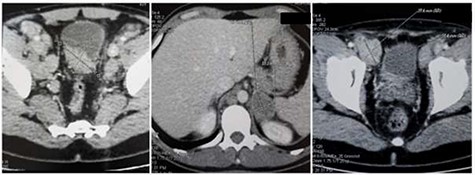

His Hematuria was first explored by abdominal ultrasound, showing an irregular wall thickening in the right lateral face and the floor of the bladder measuring 5 × 3 cm (Fig. 1) with a vascularized appearance (Color Dop and a right hydronephrosis. Computed tomography (CT) scan confirmed ultrasound findings and showed metastatic lymph nodes in both inguinal areas and in internal iliac and latero-aortic areas measuring up to 3 cm and a 4 cm mass in the left adrenal gland (Fig. 2). Digital rectal examination finds a fixed bladder floor. He underwent cystoscopy, which revealed a huge solid non-papillary black pigmented lesion located in the floor and in the right lateral face of the bladder hiding the right ureteral meatus (Fig. 3). Monopolar loop electrocautery was used to excise the tumor as a palliative treatment to stop hematuria. Tumor shavings were particularly blackish (Fig. 4). Pathological examination confirmed the diagnosis of malignant melanoma (Figs 5 and 6). The patient was actually treated with chemotherapy for a metastatic malignant melanoma. Although an evaluation CT scan showed significant progression under chemotherapy of the majority of lymph nodes, our patient is no longer complaining of hematuria or low urinary tract signs.

Abdominal CT scan: (a) wall thickening of the bladder, (b) 4 cm mass in the left adrenal gland and (c) 3 cm metastatic inguinal lymph node.